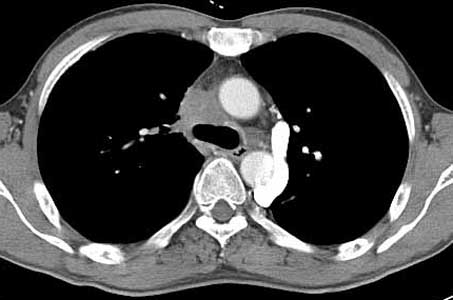

ÀÌÀü¿¡ °áÇÙ °ú°Å·Â ÀÖ´Â ³²ÀÚ 41¼¼·Î CXR ÀÌ»ó ¼Ò°ßÀ¸·Î refer